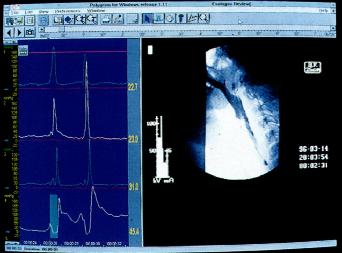

同步吞钡透视及测压检查(图2.5)

为评价吞咽异常可同步进行咽部测压及X线透视。钡透视显影与生理指标记录同步进行,检测同步显示,并以数字方式记录在同一计算机上。

图2.5同步钡透及测压检查(图取自Medtronic GastroIntestinal).

X线电视诊断

可显示钡剂通过咽部的情况并确定其是否流入气道。与咽部测压联合进行可对咽部功能紊乱的发病机制进行详细分析,效果优于单独行上述二种检查。